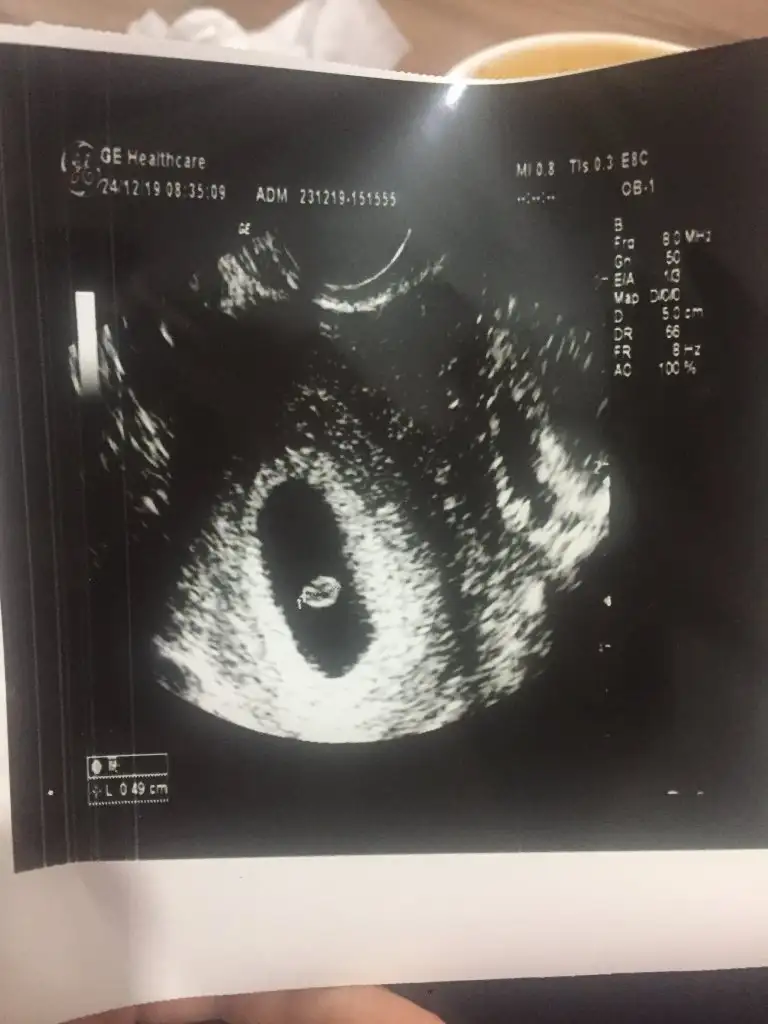

Bugün aldığım ultrason görüntüsünü de paylaşmak istiyorum.

Ve artık bebeğin kalp atışına bakalım dedi. 😔 Alttan muayene etmesine rağmen “kalp atışları çok yavaş” dedi. “Büyümüş ama kalbi istenen hızda atmıyor, 6 haftalık görünüyor; haftaya tekrar gel bir daha dinleyeceğiz, o zamana kadar kanaman olursa hemen hastaneye git” dedi.

Doktor önce karnımdan baktı. Nasıl dedim, bir şey demedi. Sonra aşağıdan bakmam gerek dedi. Uzun uzun inceledi ve bana ekranı çevirdi. Bu arada ben kalp sesi falan duymadım, kendisi de bak kalp atım sesi bu demedi. Sonra parmağıyla ekranda keseyi gösterdi “büyüme var bak burada kalbi atıyor ama yavaş atıyor. Haftaya tekrar bakacağız”dedi. Sonra ben giyindim, “kalbi yavaş atıyor haftaya tekrar dinlememiz lazım. Bu arada kanama yaşarsan hemen hastahaneye gel” dedi.